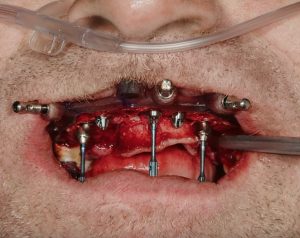

The case employed the MagnetiX™ Guided Full Mouth Rehabilitation (GFMR) system, composed of:

- Pin Positioning Guide (PPG)

- Bone Reduction Guide (BRG)

- Implant Surgical Guide (ISG)

- Provisional PMMA Restoration

These stacked magnetically, ensuring accuracy throughout each surgical step.

- After flap reflection and selective extractions, the PPG and BRG were placed and stabilized with fixation pins.

- Remaining teeth were extracted, and bone reduction was performed using the BRG.

- Six implants were placed with the ISG, ensuring angulation and hex orientation were followed precisely.

- Multi-unit abutments were seated using guide markers to confirm orientation.

Results

The entire workflow, from extractions to provisional delivery, was completed in under 90 minutes. The patient left with a fixed, esthetic, and functional restoration.